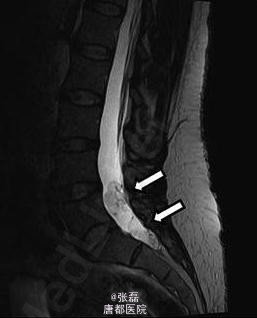

患者女性,46 岁,因头疼加重 2 周住院。住院时表现为颈部僵硬,伴有眩晕。头颅 MRI 未见明显异常。脑脊液结果示:中性粒细胞 133 个 /μl,嗜酸性粒细胞 38%。血清囊虫抗体滴度 106(正常≤0)。 脊髓 MRI 示:颈部单发囊性占位,腰部蛛网膜下腔多发囊性占位。故诊断为脊髓囊虫病,给予阿苯达唑 (2×400 mg/ 天) 驱虫、激素(强的松 60 mg/ 天)抗炎治疗 4 周。治疗期间,患者症状明显缓解,但是在随访 6 个月时,颈部疼痛仍未见缓解,MRI 示颈部囊性占位体积有所增大。